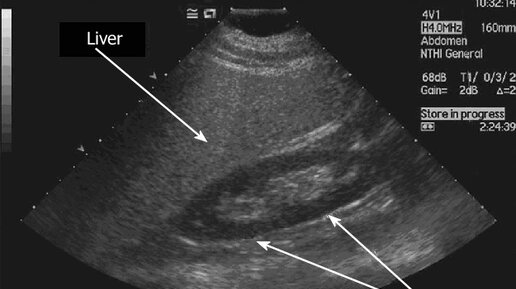

УЗИ ПЕЧЕНИ: анатомия сегментов, ультразвуковая анатомия, варианты нормы и разбор кисты печени.

Ультразвуковая диагностика печени (УЗИ печени) широко используется в современной медицине для оценки состояния органа у пациентов с подозрением на специфические заболевания. Это отличный диагностический инструмент, к которому врачи прибегают в первую очередь. Диагностическая методика применяется, если: ✔️ при жалобах на боли в правом боку; ✔️ наблюдается желтушность кожного покрова; появился зуд; ✔️ анализ крови показывает высокие уровни показателей АСТ, АЛТ и билирубина; ✔️ при травмах живота...